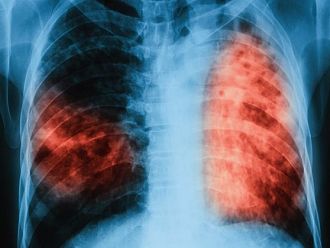

„Дни на Отворени врати” за безплатни прегледи за туберкулоза стартират в лечебните заведения за диагностика и лечение на туберкулоза в седмицата 19-23 юни 2017 г.

По време на дните на Отворени врати на всеки желаещ се предлага скрининг за риска от туберкулоза чрез анкета и консултация с лекар. На съмнителните за туберкулоза лица се извършват прегледи и допълнителни медицински изследвания.

„Дните на Отворени врати“ са ежегодна проява, която стартира през 2009 г. По време на проведената кампания в периода от 2009 г. до март 2017 г. броят на анкетираните за туберкулоза лица е 93 509, като бяха открити 1039 лица с туберкулоза и 3650 лица с латентна туберкулозна инфекция. Данните сочат, че се постига добра разкриваемост на случаите на туберкулоза и латентна туберкулозна инфекция.

По време на проведените през месец март 2017 г. „Дни на Отворени врати” броят на анкетираните за туберкулоза лица е 3392, от тях 37 лица са открити с туберкулоза и насочени своевременно за лечение, а 189 са открити с латентна туберкулозна инфекция и са обхванати с химиопрофилактика.